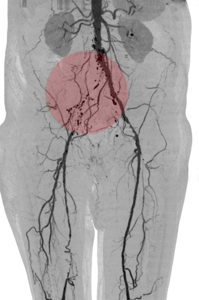

6. Fibrinolyse – medikamentöses Auflösen von Blutgerinnseln

Gefäßverschließende Blutgerinnsel können auch durch Medikamente aufgelöst werden, um den Blutfluss wiederherzustellen. Damit dieses Medikament sicher und effektiv wirken kann, wird es über einen Katheter direkt zum Verschluss gebracht. Das erfolgt über eine langsame mehrstündige Gabe. Zur Verbesserung der Wirkung kann durch Spezialkatheter das Medikament mit Hilfe von Schallwellen in das Blutgerinnsel transportiert werden.